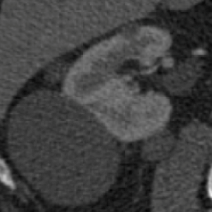

Patients diagnosed with an RCC usually get a CT-scan to assess the anatomy of the renal vasculature and the size and position of the tumour. This information, which consists of a stack of 2D-images as can be seen in Figure 2, is nowadays used to plan the clamping strategy. Using segmentation software, this 2D information can be segmented and 3D models can be generated, as shown in Figure 3. This results in a 3D visualisation of the kidney, the tumour, the blood supplying arteries and the relevant surrounding structures. Based on this information, surgeons can virtually test and optimize their approach using the planning tool software, e.g. giving estimations of the amount of viable and functional kidney tissue left after the procedure.